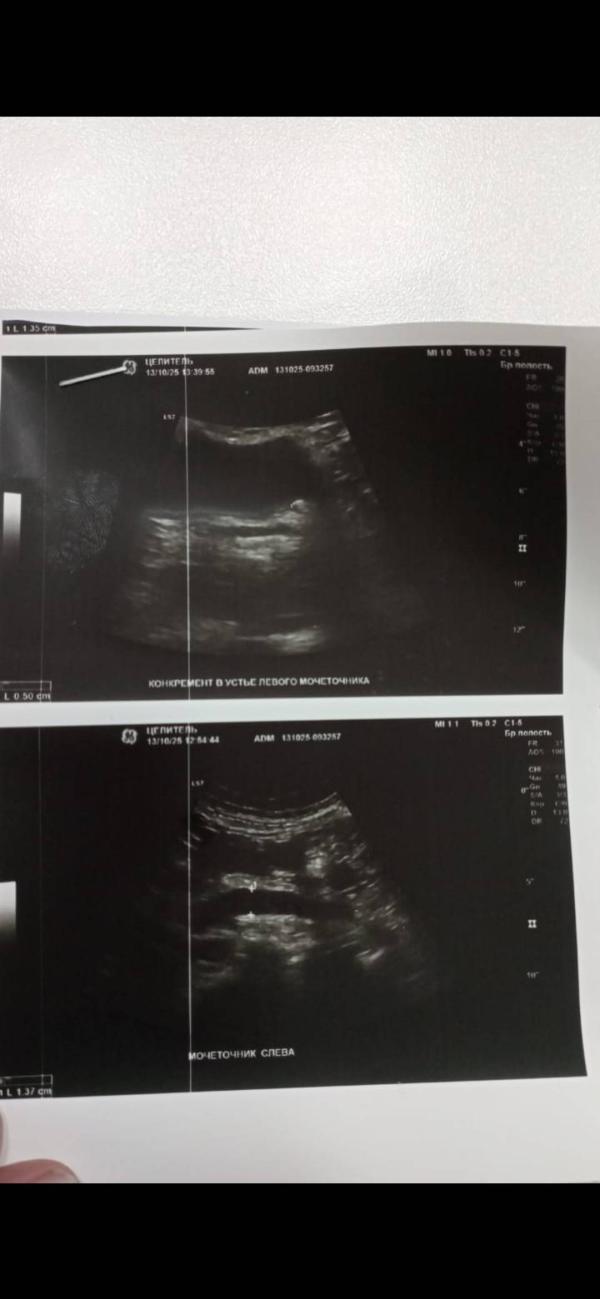

У нее приступ был? По УЗИ почечная колика, там камушек выходит 5мм слева